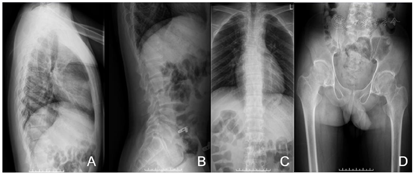

先证者X线检查表现为:左桡骨小头骨性突起,骨小梁稀疏,骨端膨大,肘关节关节间隙狭窄;骨盆局部骨质增生变尖,双侧股骨头骨质密度不均,骨端膨大,关节间隙变窄;脊柱侧弯,部分椎体扁平,呈鸟嘴样。该PPD患者无智力障碍,无听力、视力、嗅觉受损。先证者家庭成员临床表型正常(图1、图2)。

PPD先证者为15岁男性,该患者10岁起病,出现双肘关节畸形,无法伸直。12岁开始髋关节活动障碍、运动迟缓、行走摇摆,下蹲困难,指间关节膨大。其X线表现为左桡骨小头骨性突起,骨小梁稀疏,骨端膨大,肘关节关节间隙狭窄;骨盆局部骨质增生变尖,双侧股骨头骨质密度不均,骨端膨大,关节间隙变窄;脊柱侧弯,部分椎体扁平。先证者足月顺产,其父母非近亲结婚,父母和两个姐姐均健康,家族中无类似病例。就诊时身高158.9 cm,体重54kg,臂展150 cm,上部量82 cm,下部量76.9cm。